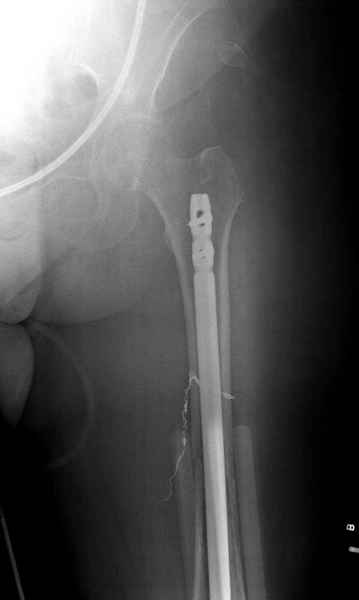

Здесь случай 66 летней пациентки со спонтанными болями в левой нижней конечности, обратилась в приемное, сделаны снимки бедра и КТ.

Патологический перелом бедра, конечность на вытяжении.

Известно, что многие из нас независимо от метода лечения и стадии первичной опухоли проводят интрамедуллярное штифтование при различных патологических состояниях бедра, включая патологические переломы.

С минимальным рассверливанием и ретроградным методом провели остеосинтез бедра 12 мм гвоздем. (17-20)

Кровопотеря во время операции меньше 100 мл.